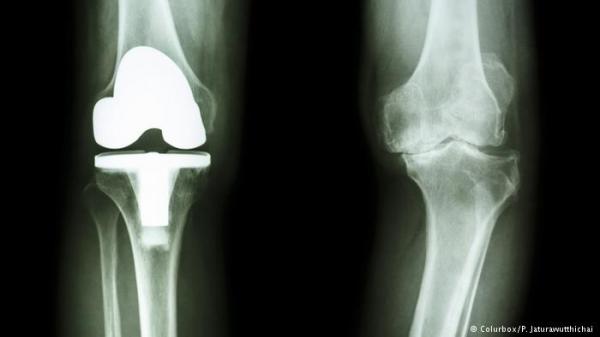

يعاني بعض الناس من مشاكل في الركبة وفي المفاصل، فيتعذر عليهم المشي والحركة والانحناء بصورة طبيعية. التكنولوجيا الحديثة وجدت حلا لهذه المشكلة واستطاع العلماء بالتعاون مع الأطباء تصنيع مفاصل صناعية حسب الطلب.

ويمكن عبر التكنولوجيا الجديدة استبدال مفاصل جميع المرضى المصابين بتلف في العظام، أو مفاصل المصابين في الطبقة السطحية للغضروف خاصة بعد تعرضهم لحوادث. وكذلك في الحالات التي يصعب فيها إعادة الغضروف لطبيعته أو عندما لا يؤدي العلاج إلى وضع حد للألم بعد عمليات الترميم بسبب خلل في الفخذ، فيكون المصابون بحاجة إلى زراعة مفصل اصطناعي، كما أضاف الدكتور تيلو جون.

عملية زراعة المفصل الجديد نجحت مع بياتريس. ولكن على الأطباء أولا وقبل القيام بالعملية إجراء تصوير طبي دقيق للركبة. وأخذ صور للركبة على شكل طبقات محورية وتخزينها في برنامج خاص. ثم يقوم البرنامج بتحويل البيانات إلى نموذج ثلاثي الأبعاد للركبة والمفصل.

من مميزات التقنية الجديدة هو أن المادة العظمية التي يجب إزالتها في المفصل أقل بكثير مقارنة بعمليات العلاج التي كانت تُجرى في السابق، كما أوضح البروفيسور بيرند ديتريش كاتهاغن أخصائي جراحة العظام. وأضاف البروفيسور الألماني لـDW: "العظام لها ارتفاع وعرض وسماكة وعندما أخذ مفصلا جاهزا لا يكون العرض والسماكة مناسبين دائما. كذلك ليس لدينا مفاصل تكون مناسبة جيدا من حيث السطح الخارجي". بينما الطريقة الجديدة تعمل على تصنيع مفصل مناسب حسب قياسات ركبة المصاب. وحتى مستلزمات العملية تجري طباعتها أيضا عبر تقنية الطباعة الثلاثية الأبعاد، وهو ما يوفر الوقت للعملية ويسبب نزيفا وآلاما أقل.